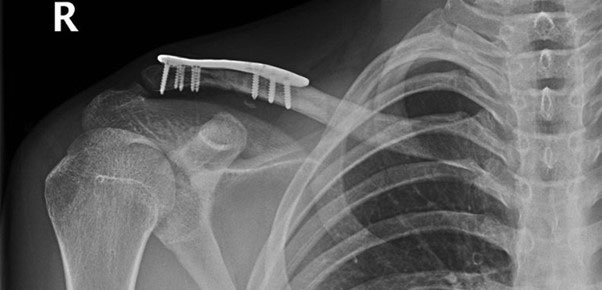

Once again, he was going well and back into his sport when again he fell – this time fracturing the distal end of the clavicle, just next to the plate that I had put in in July of the preceding year (see image 4 below).

Fracture of distal clavicle next to existing plate after fall from mountain bike